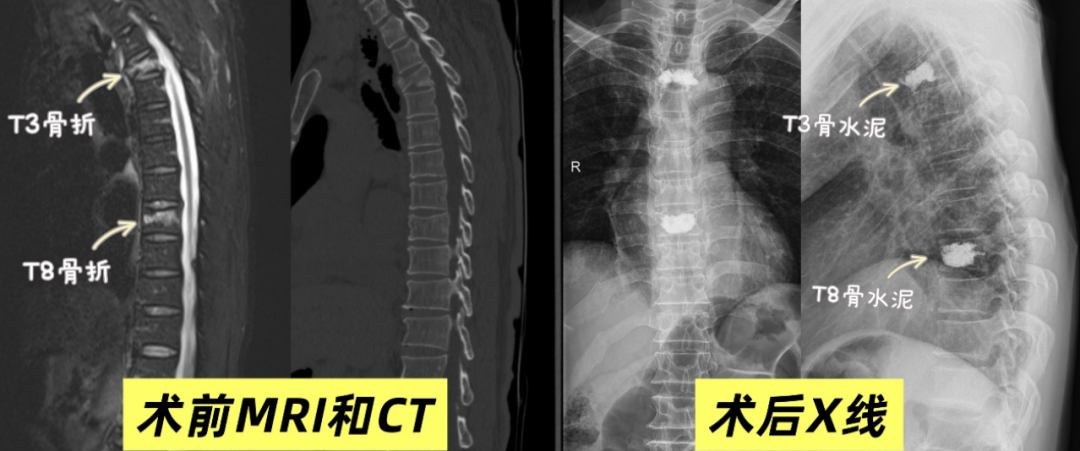

患者因外伤突发剧烈胸背部疼痛,活动严重受限,入院后确诊为胸椎新鲜压缩性骨折(T3、T8),合并严重骨质疏松。上胸椎解剖结构特殊,椎弓根纤细、紧邻核心脏器,穿刺定位难、风险高,被业内称为椎体成形术“相对禁区”。患者高龄、基础状况弱,传统手术与保守治疗均存在诸多风险,治疗陷入两难。

骨科团队启动多学科术前评估,依托CT三维重建与术中C臂引导,制定个体化穿刺方案。在科室主任马骏,驻酒专家、科室执行主任唐国柯的带领下,团队凭借精准操作,顺利完成双椎体穿刺、骨水泥灌注,全程耗时约50分钟,微创无痕、几乎无出血,手术圆满成功。

术后患者疼痛显著缓解,视觉模拟疼痛评分从9分降至2分,当天即可下床活动,次日顺利出院,打破“伤筋动骨一百天”的传统认知。此次手术的成功,彰显了科室微创技术实力,也为高龄高危患者带来康复希望。